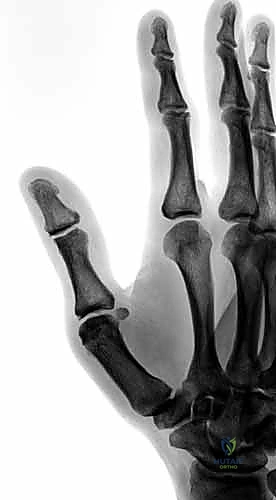

2. التصوير بالأشعة السينية (X-rays)

يُعد التصوير الشعاعي الخطوة الأولى لاستبعاد وجود كسور مصاحبة. في كثير من الأحيان، ينسلخ الرباط ويسحب معه قطعة صغيرة من العظم (Avulsion fracture). كما يتم أخذ صور أشعة تحت الإجهاد (Stress X-rays) لتوثيق عدم الاستقرار.